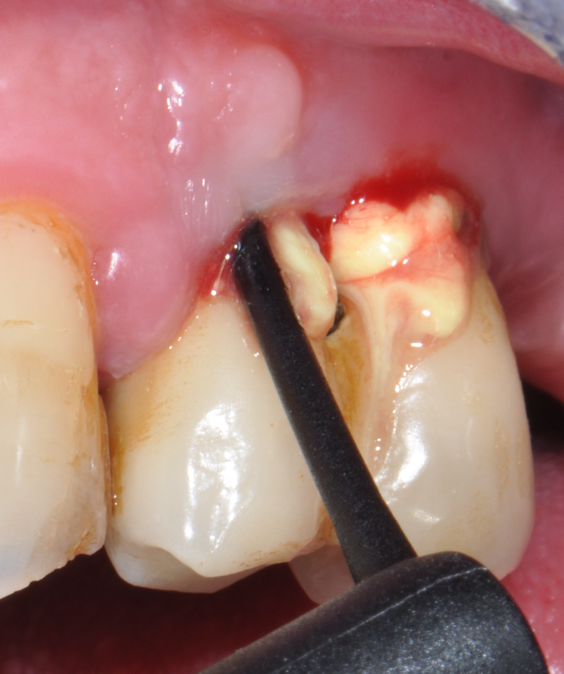

The parameters used to define peri-implant disease usually are: Probing Depth (PD), Crestal Bone Loss (CBL), Bleeding on Probing (BOP) and presence of suppuration and/or fistula.9 Peri-implant mucositis is characterised by soft tissues inflammation witnessed by BOP with or without PD deepening but no effects on the crestal bone while peri-implantitis is characterised by CBL, BOP alone or in conjunction with pus, with or without PD deepening. (Figs. 1, 2 and 3) display the diagnostic steps of a case of peri-implantitis. While mucositis allows a complete healing, peri-implantitis is not reversible.12

Fig.2: Case 1. BOP starts immediately after probing.